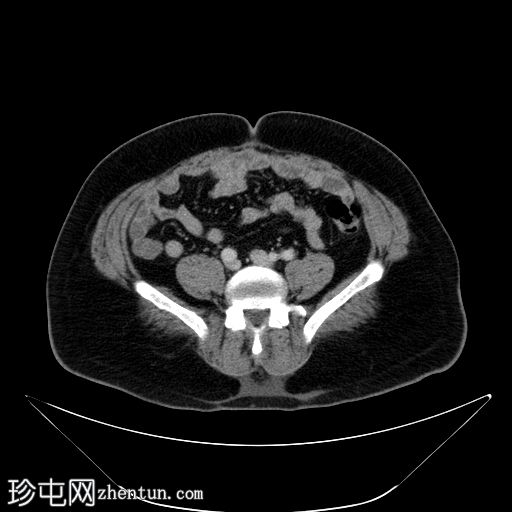

冠状位增强扫描(门静脉期)

弥漫性阴茎水肿,阴茎海绵体内积液伴气体,腹股沟淋巴结肿大。